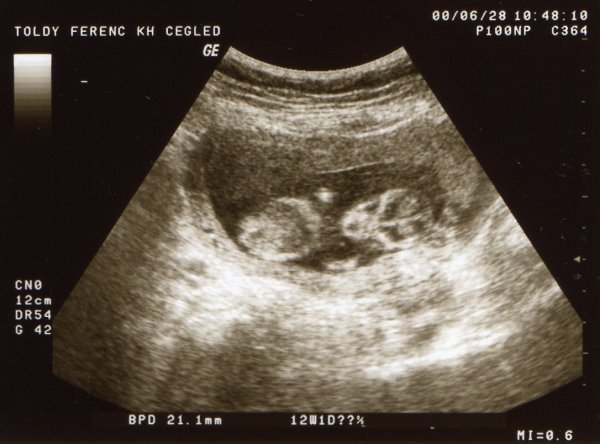

Saxi, Mica! Gratulálok a kis pocaklakókhoz és nagyon jó egészséget, boldog pocakosodást kívánok nektek!!!!